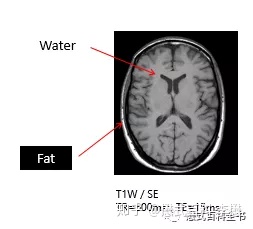

如上图所示,是一个头颅的T1WI,非常常见。我们用前面所学的知识。液体(脑脊液)是长T1的,在T1WI中,应该是低信号,是暗的,所以图中,脑脊液是黑色的;而脂肪组织是短T1的,在T1WI中,是高信号,是白的,所以图中,头皮脂肪是亮的。

液体(水),在T1WI上是黑的(暗的),在T2WI上是白的(亮的);

脂肪组织,在T1WI上是亮的,在T2WI上也是亮的;

其他的还有,骨皮质,在T1WI上是黑的,在T2WI上也是黑的;